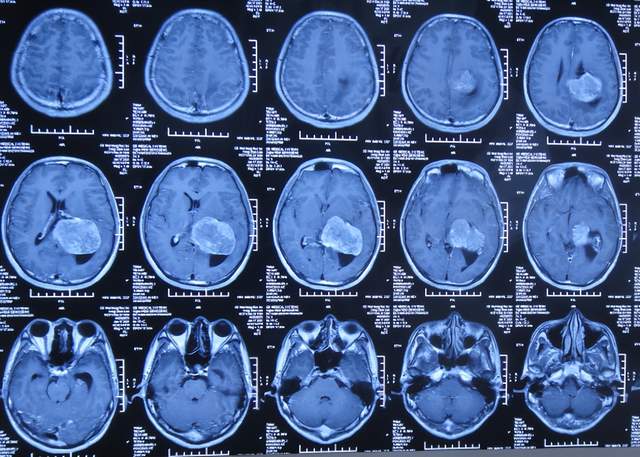

直到2021年1月8日(间断头痛4年后),因无法忍受头痛,就诊于山东省济南市商河某医院,查头颅核磁示颅内占位(图-1)。

图-1:2021年1月8日头颅核磁

为治疗脑瘤,于5天后即2021年1月13日,就诊于山东省某省级三甲医院,查头颅核磁增强(图-2)和头颅血管造影(图-3)示颅内占位。

图-2:2021年1月13日头颅核磁增强

入院后5天即2021年1月18日,查头颅CT增强示颅内占位(图-4)。

图-4:2021年1月18日头颅CT增强